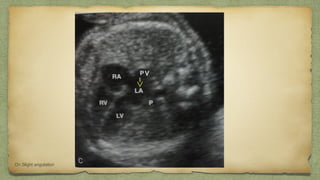

๏ฑThe ultrasound beam is directed

perpendicular to the midchest

plane at the level of the heart.

๏ฑ These chambers consist of the

right and left atrial and both

ventricular chambers

๏ฑCorresponding valves between

them

Four-Chamber View

v

On Slight angulation